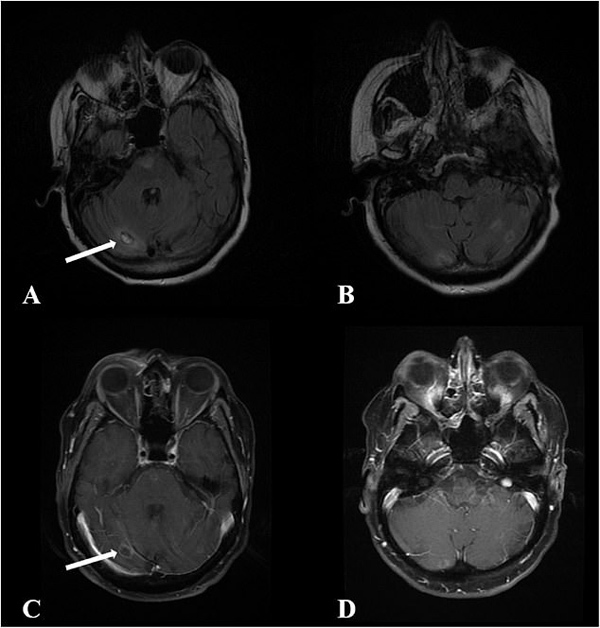

Một lần khác, bà đến bệnh viện ở Seattle và bỗng nhiên lên cơn động kinh co giật, mất đi nhận thức dù trước đó hoàn toàn tỉnh táo. Nhận ra có điều không ổn, các bác sĩ tại đây đã tiến hành chụp CT. Hình ảnh não của bà được nhìn thấy trên tấm phim nhiều phần đã trở nên mềm nhão và chỉ toàn màu máu.

Não của bà dần bị ăn mòn bởi vi khuẩn amip.

Dù bệnh nhân lập tức được điều trị bằng thuốc và kháng sinh nhưng đã quá trễ. Trong vòng một tuần, cô rơi vào tình trạng hôn mê sâu, bộ não đã gần như mất hết hình dạng và trở nên mềm nhũn, tỉ lệ cứu sống là rất thấp. Gia đình quyết định để bà ra đi không lâu sau đó.